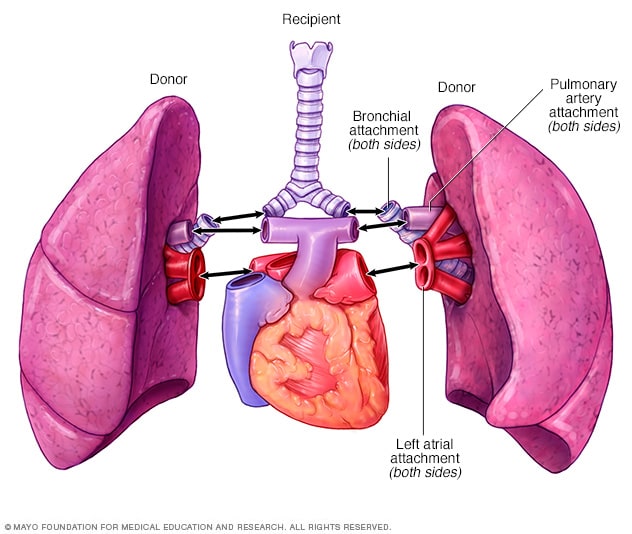

Trasplante de los dos pulmones

Trasplante de los dos pulmones

Durante un trasplante de los dos pulmones, los cirujanos extirparon los pulmones enfermos, uno por vez, y luego unieron los pulmones del donante a las vías aéreas y a los vasos sanguíneos que entran y salen del corazón.

El cirujano hará un corte en el pecho para extraer el pulmón dañado. Las vías respiratorias principales conectadas a ese pulmón y los vasos sanguíneos que se encuentran entre ese pulmón y el corazón se conectarán al pulmón donado. En algunos trasplantes de pulmón, es posible que se te conecte a una bomba de circulación extracorpórea, que hace circular la sangre durante el procedimiento.